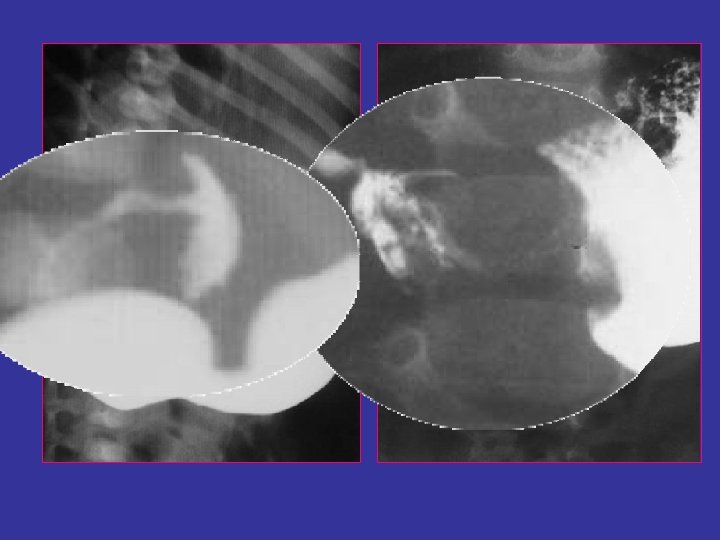

TOGD • N’est pas systématique : - symptomatologie atypique - échographie non concluante • Signes indirects : - dilatation et stase gastrique - estomac de lutte - retard de passage transpylorique • Signes directs ( pathognomoniques) : - défilé pylorique - image en parenthèses

TOGD • RGO associé